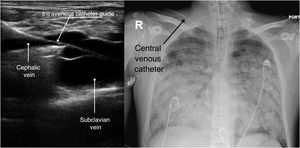

A 33-year-old male was admitted to the Intensive Care Unit due to respiratory distress secondary to Legionella pneumonia, requiring neuromuscular block and prone decubitus upon admission. We conducted prior ultrasound-guided catheterization of the right cephalic vein at its final portion where the vessel drains into the subclavian vein. The Fig. 1 and Video 1 show a longitudinal view of the catheter guide crossing the junction of the cephalic and axillary veins towards the right subclavian vein. Correct positioning was confirmed radiographically (Fig. 1). Such catheterization offers an ultrasound-guided alternative to the infraclavicular subclavian vein, which is not always accessible to ultrasound, posing an increased risk of pneumothorax that should be avoided in patients with severe respiratory failure. On the other hand, positioning is more accessible during prone decubitus compared with other venous accesses (Supplementary images).